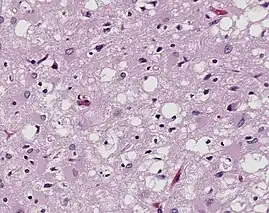

%252C_H%2526E.jpg)

Prions are misfolded proteins that are transmissible and can influence abnormal folding of normal proteins in the brain. They do not contain any DNA or RNA and cannot replicate other than to convert already existing normal proteins to the misfolded state. These abnormally folded proteins are found characteristically in many neurodegenerative diseases as they aggregate the central nervous system and create plaques that damages the tissue structure. This essentially creates "holes" in the tissue. It has been found that prions transmit three ways: obtained, familial, and sporadic. It has also been found that plants play the role of vector for prions. There are eight different diseases that affect mammals that are caused by prions such as scrapie, bovine spongiform encephalopathy (mad cow disease) and feline spongiform encephalopathy (FSE). There are also ten diseases that affect humans, such as Creutzfeldt–Jakob disease (CJD)[20] and Fatal familial insomnia (FFI).